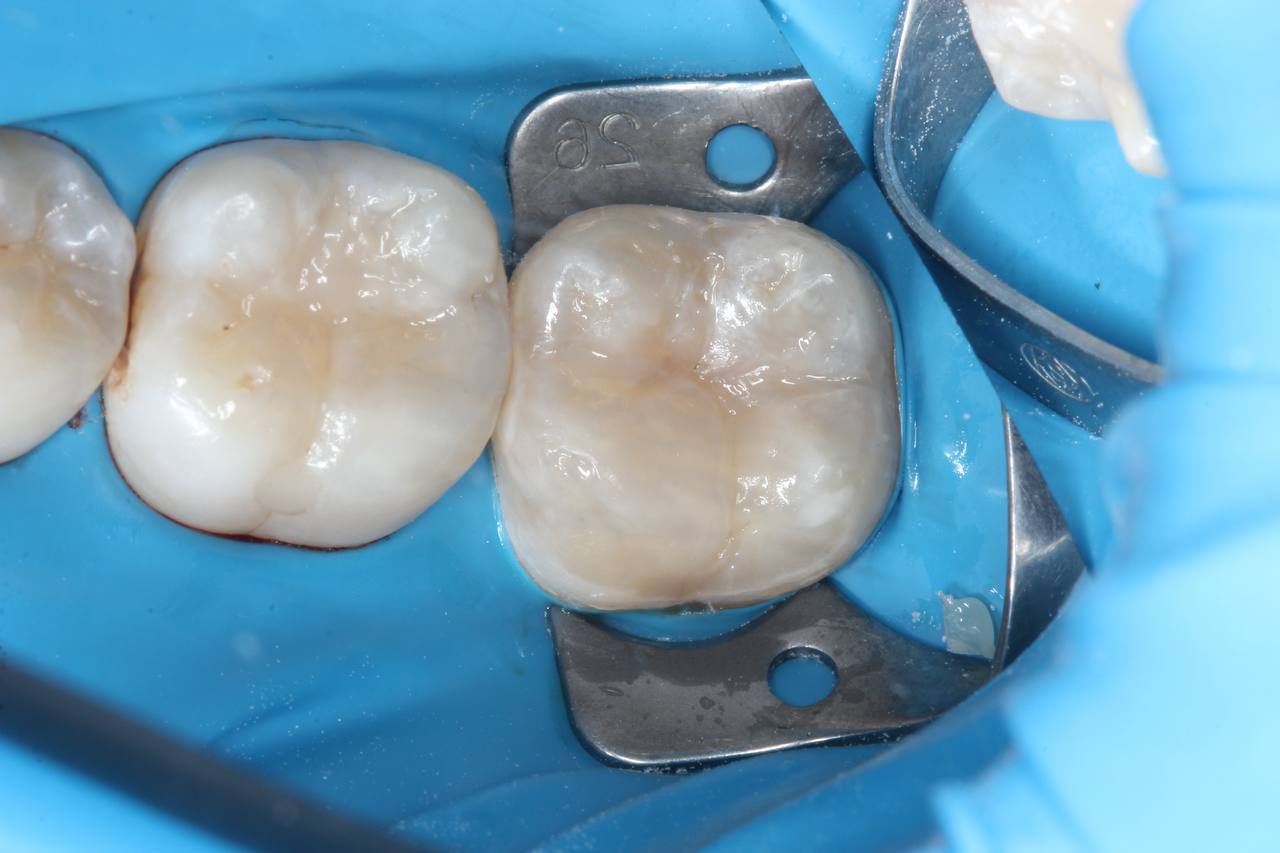

1. анестезия, препарирование кариозной полости

2. восстановление композитным материалом анатомической формы зуба

Результат

Здоровые, функциональные зубы